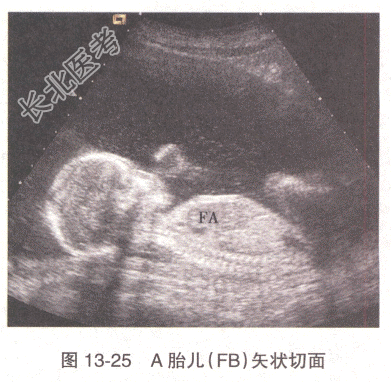

患者,女性,31岁。孕2产0,孕22周,感觉腹胀1周。无阴道流血及流水史。孕12周时超声检查示宫内妊娠,单绒毛膜囊双羊膜囊双活胎,A胎儿NT0.32cm,B胎儿NT0.12cm。22周超声检查,双胎儿解剖结构均未见明显异常,其余超声见图13-24~图13-27。

E、B胎儿为供血儿,羊水过少,贴附子宫前壁

B、B胎儿为受血儿,羊水过少,贴附子宫前壁